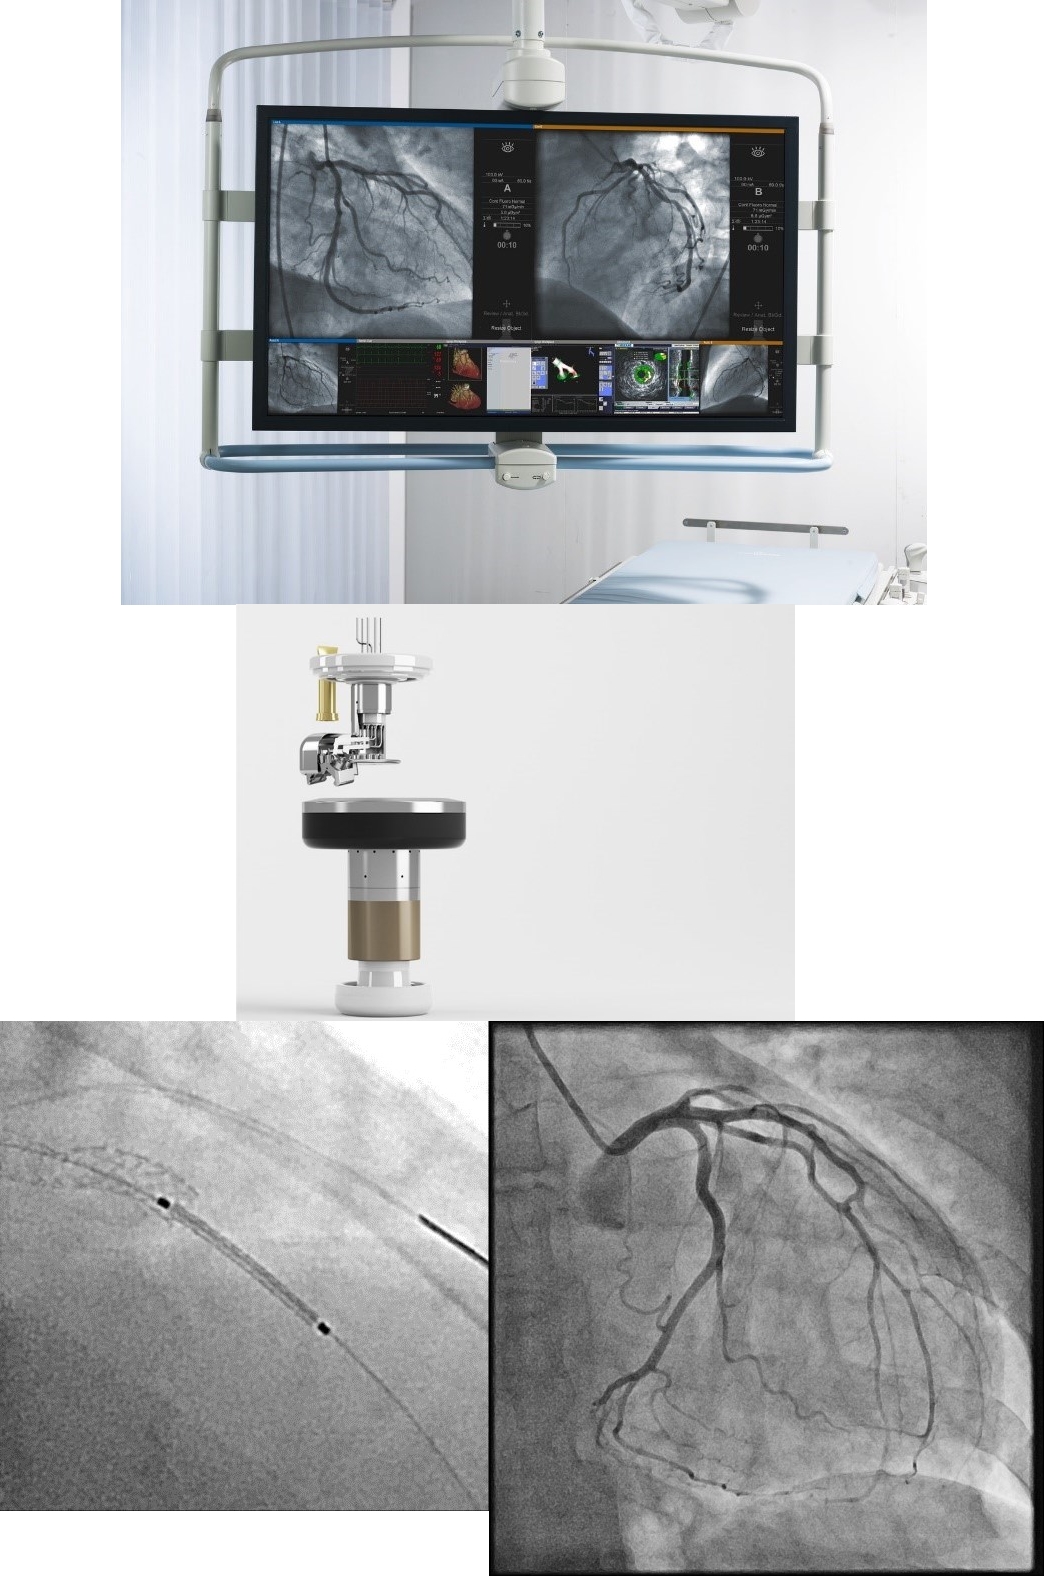

最新型血管撮影装置

この血管撮影装置は、血管内に細かい管(カテーテル)を挿入し、造影剤を注入することで、微細な血管病変(狭窄、がん等)の診断を可能にします。

さらに治療に役立つ多くの機能を搭載し、検査を受ける方の放射線被ばく低減も十分に考慮したシステムですので、安心して検査・治療を受けていただけます。

最新技術のFlat Emitterテクノロジーを搭載し、従来型に比べX線の発生エリアをより小さく、正方形に近い形を実現し、効率的なX線を得ることが可能になるため、少ない線量で高画質な画像情報を得ることが可能になりました。

これにより患者様への被ばく線量も大幅に低減することが可能になります。さらに大型の統合型マルニモニタを採用し、診断・治療に必要な情報を一元的に確認することが可能になり、血管撮影装置のみの情報だけではなく、術前のCT画像やリアルタイムの血管内超音波装置の画像情報・心電図波形や電子カルテ情報の表示など多くの医療情報を基に精度の高い診断・治療を実現します。

最新の手技支援機能として、『CLEARstent Live』というリアルタイムのステント強調機能を搭載しています。最新の血管内治療の手技においては、使用する血管拡張のためのステント素材が患者様への影響を最小限にするため、非常に薄い素材に変わりつつあります。

この機能は最新のステントの視認性をリアルタイムに向上させる手技支援機能になり、患者様の治療の精度の向上のみならず、低侵襲検査を実現します。